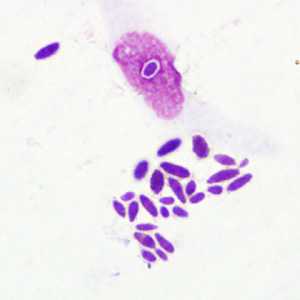

February - 2008 - Case #222

Images were taken from a thick blood smear stained with hematoxylin from an adult male from Cameroon. The following images, A-C were all captured from the same field of view.